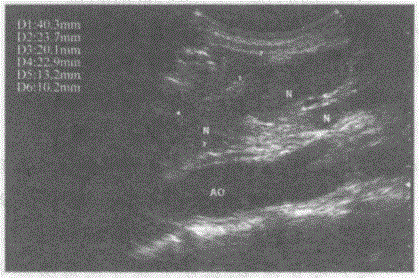

临床资料:男,50岁,肺癌术后肝转移。超声综合描述:腹主动脉前方可见多个大小不等低回声,最大4.0cm×2.3cm,边界尚清晰,形态不规则,部分相互融...

问题 临床资料:男,50岁,肺癌术后肝转移。 超声综合描述:腹主动脉前方可见多个大小不等低回声,最大4.0cm×2.3cm,边界尚清晰,形态不规则,部分相互融合。 超声提示:

选项 A.腹腔多发肿大淋巴结(淋巴结转移癌) B.腹膜后畸胎瘤 C.胃癌 D.平滑肌肉瘤

答案 A